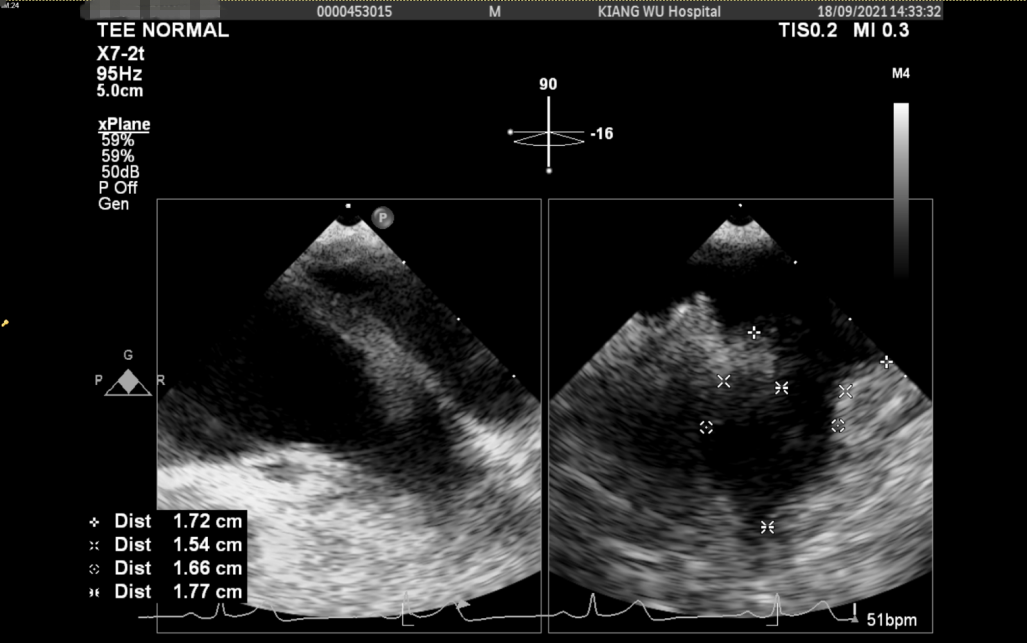

食道超声及左心耳造影

经造影及食道超声检查后释放WATCHMAN FLX左心耳封堵器